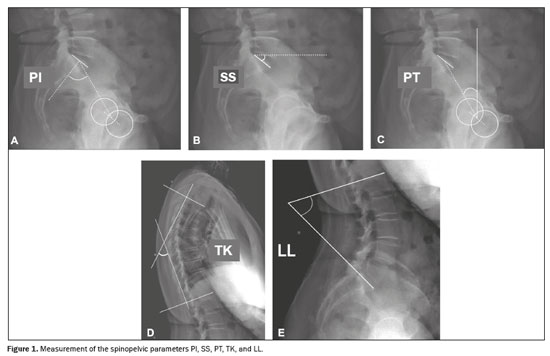

To measure the spinopelvic parameters and vertebral curvature angles, we used Surgimap software (Nemaris Inc., New York, NY, USA). The following parameters were evaluated (Figures 1 and 2): sacral slope (SS); pelvic tilt (PT); pelvic incidence (PI); lumbar lordosis (LL); thoracic kyphosis (TK); sagittal vertical axis (SVA); spinosacral angle (SSA); T1 pelvic angle (TPA); and global tilt (GT). The SS corresponds to the angle formed between the upper endplate of S1 and a horizontal line. The PT corresponds to the angle formed between a vertical line originating at the center of the femoral head and a line running from the center of the femoral head to the midpoint of the S1 endplate. The PI corresponds to the angle formed by a line running perpendicular to the sacral plateau and a line connecting its midpoint with the center of femoral rotation. The degree of LL is determined by measuring the Cobb angle from the superior endplate of S1 to the superior endplate of L1. The degree of TK is determined by measuring the Cobb angle from the inferior endplate of T12 to the superior endplate of T1. The SVA is the measurement of the horizontal distance between the plumb line of C7 and the vertical line passing through the posterosuperior point of S1. The SSA corresponds to the angle formed between the line passing from the center of C7 to the center of the endplate of S1 and the surface of the sacral endplate. The TPA corresponds to the angle formed by a line running from the geometric center of the femoral heads to the center of the T1 vertebral body and a line running from the geometric center of the femoral heads to the center of the superior endplate of S1. The GT is defined as the angle formed by a line running from the center of the superior sacral endplate to the center of the C7 vertebral body and a line running from the geometric center of the femoral heads to the center of the sacral endplate(15). The contours of the femoral heads were marked, and lines were drawn adjacent to the superior plateau of S1, superior plateau of L1, inferior plateau of T12, superior plateau of T1, and inferior plateau of C2. From those markings, the software automatically calculated the spinopelvic parameters and vertebral curvatures.